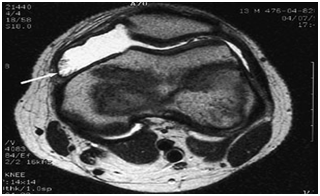

The classic plain radiographic findings of PVNS consist of cystic erosions, increased density of the synovium, secondary to hemosiderin deposition and peri-articular soft-tissue swelling with no calcification.8 Magnetic resonance imaging usually demonstrates key diagnostic features, which include joint effusion, elevation of the joint capsule, hyperplastic synovium and low signal intensity resulting from hemosiderin deposition.2 In patients with diffuse pigmented villonodular synovitis of the knee, magnetic resonance imaging (MRI) may show a large effusion, low signal intensity on both T1 and T2 weighted images (because of hemosiderin deposition), hyperplastic synovium and occasional bony erosions (Figure 1) and (Figure 2).

Figure 1 T2-weighted magnetic resonance image (MRI) of the knee in a patient with pigmented villonodular synovitis. The scan shows a large effusion and villous proliferation arising from the synovial lining (arrow).